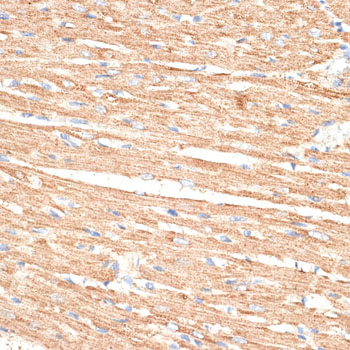

Immunohistochemistry of paraffin-embedded rat heart using KLHL9 at dilution of 1:100 (40x lens).